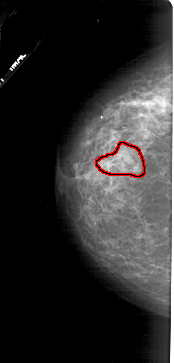

A_1730_1.LEFT_CC

LEFT_CC LINES 5071 PIXELS_PER_LINE 2431 BITS_PER_PIXEL 12 RESOLUTION 43.5 OVERLAY

FILE: A_1730_1.LEFT_CC.OVERLAY

TOTAL_ABNORMALITIES 1

ABNORMALITY 1

LESION_TYPE CALCIFICATION TYPE PLEOMORPHIC DISTRIBUTION SEGMENTAL

ASSESSMENT 4

SUBTLETY 3

PATHOLOGY MALIGNANT

TOTAL_OUTLINES 1

BOUNDARY